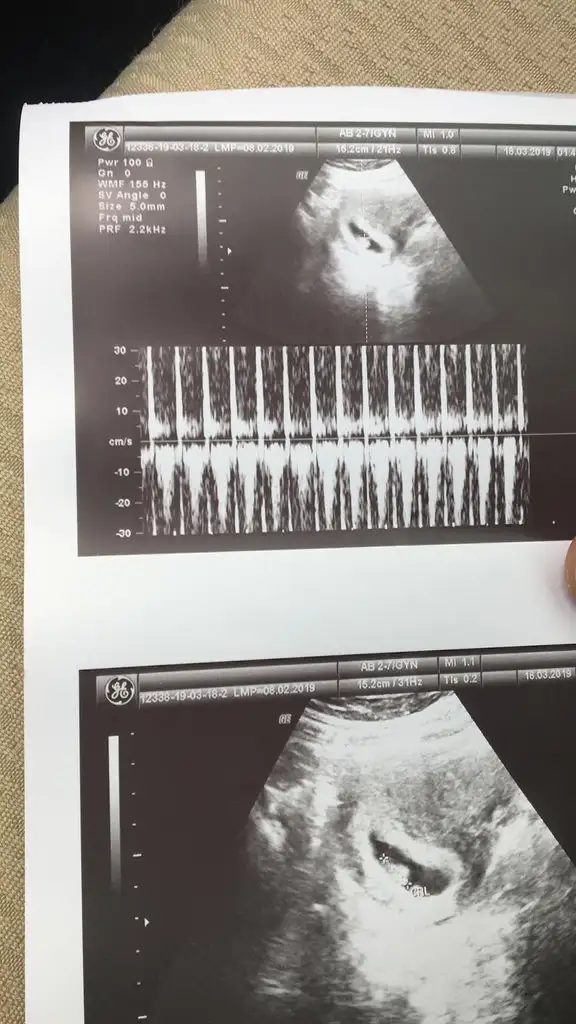

Erkek tahminimce.Merhaba bize de yorum yapabilirmisiniz.

10+5 haftalik goruntusu

Tesekkurler